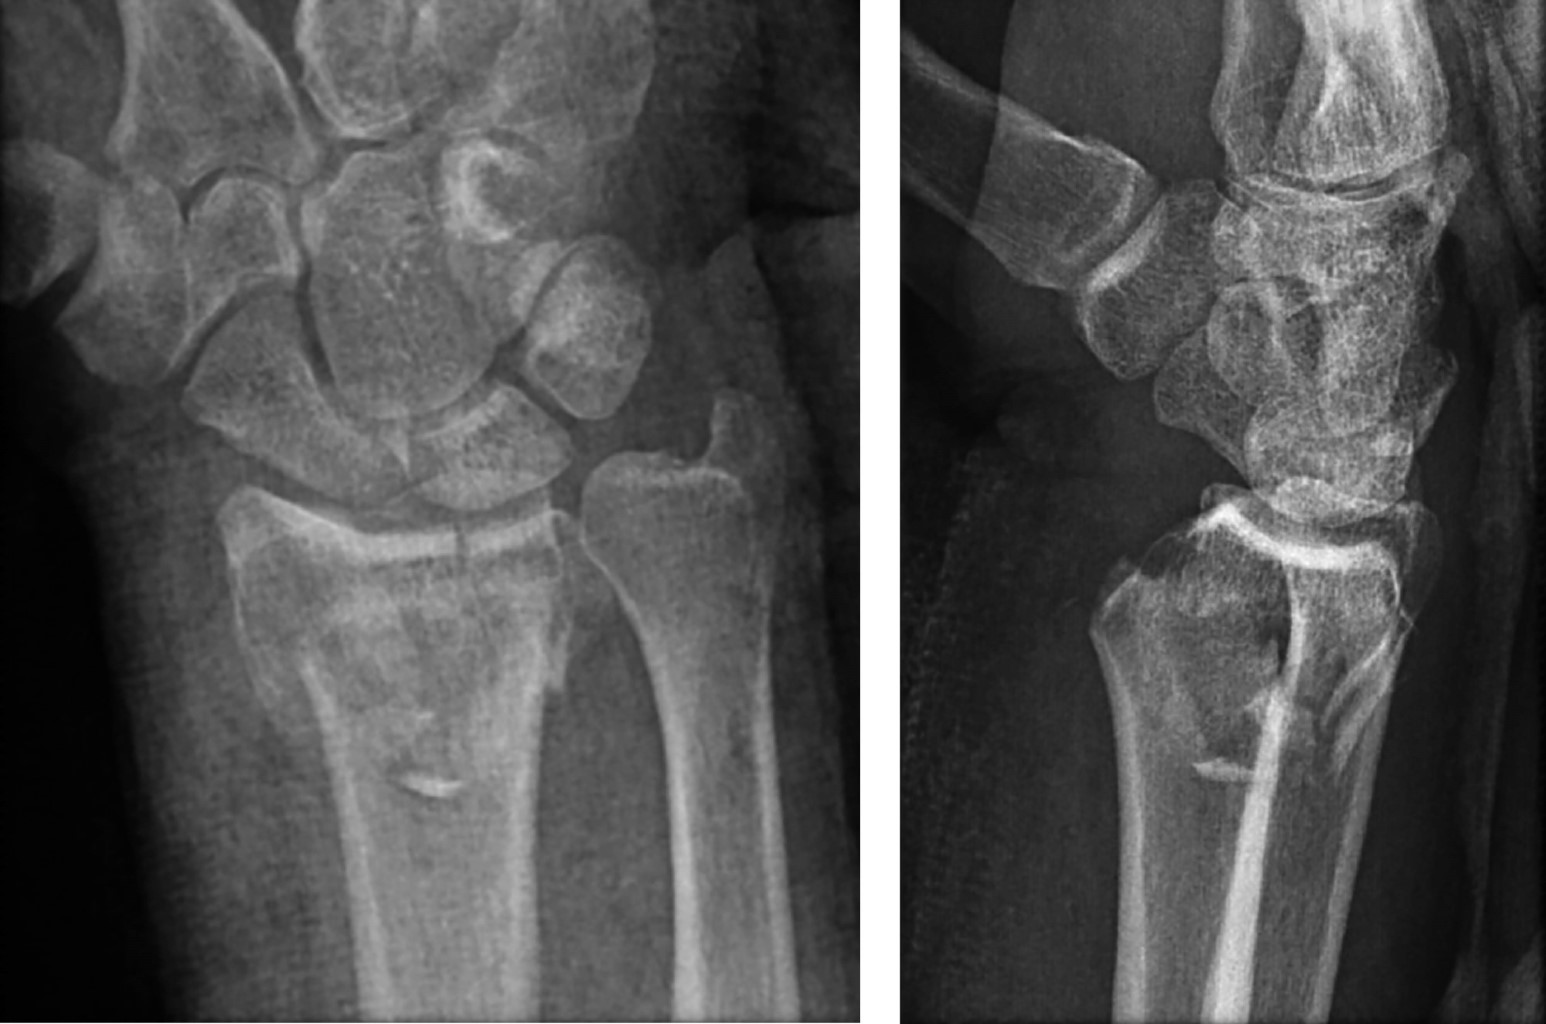

Introducción: las fracturas desplazadas de extremo distal del radio se acompañan frecuentemente de manifestaciones clínicas sugestivas de neuropatía del nervio mediano. El diagnóstico diferencial debe incluir la contusión o lesión nerviosa directa, el síndrome del túnel carpiano agudo, el síndrome compartimental del antebrazo o la exacerbación de un síndrome del túnel carpiano idiopático. Caso clínico: un varón de 44 años presentó una fractura del radio distal derecho tras un accidente de motocicleta. Presentaba una herida contusa de 1.3 cm situada proximalmente al pliegue de flexión radiocarpiano y refería disestesias bien definidas en el territorio sensitivo del nervio mediano. La fractura se trató mediante reducción abierta y osteosíntesis con placa volar y, por los hallazgos en la exploración inicial, se exploró el nervio mediano encontrando una sección completa con un defecto de 2.0 cm. Se liberó el túnel carpiano y se interpuso un injerto fascicular de nervio sural que presentó buenos resultados en el seguimiento final. Conclusión: la sección del nervio mediano tras una fractura de muñeca es una lesión extremadamente rara. Este caso clínico subraya la importancia de una exploración física inicial minuciosa incluyendo la evaluación neurológica inicial.

Figura 1